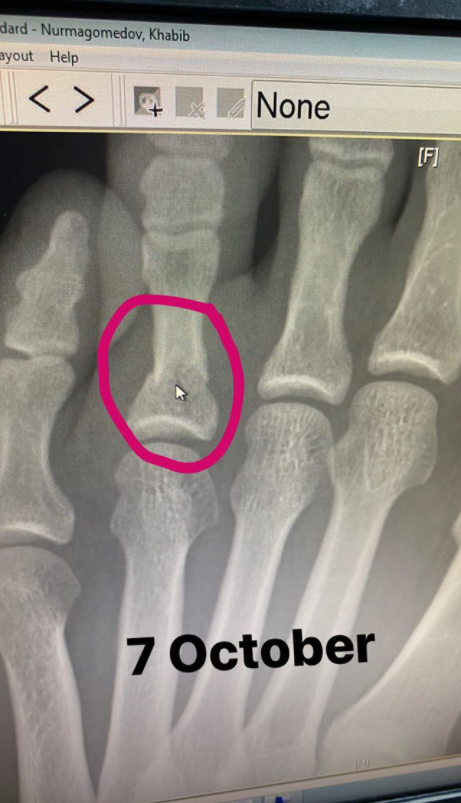

Чемпіон в легкій вазі Хабіб Нурмагомедов підтвердив, що за кілька тижнів до бою з Джастіном Гейджі поламав палець.

Дагестанець виклав в Instagram рентген-знімок свого пальця лівої ноги, на якому стоїть дата 7 жовтня.